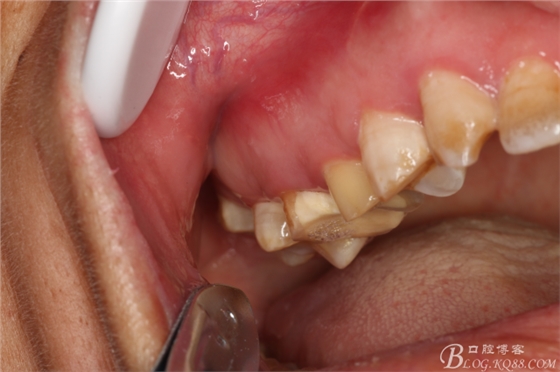

圖1.術(shù)前患者的口內(nèi)照片:15、16頰側(cè)黏膜膨隆、捫診有乒乓感